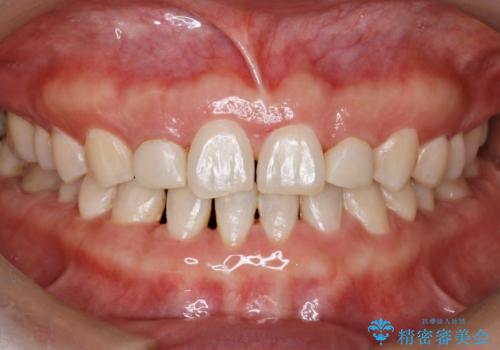

歯の形気になる!! セラミック治療 前歯( エクセレント)

- 歯の形が気になるということで以前入っていたプラスチックのものから、セラミックでの治療を希望されたので行いました。

色や形をこだわりたいということで、当院最上位ランクのエクセレントにて治療を行いました。

以前使用していた被せ物を除去して、仮歯に置き換えます。

その後、歯の最終的な形を作って型取りを行います。

当院で患者様の口腔内の写真を撮影し技工士さんに指示を出して完成します。

患者様はかなり喜ばれておりました。